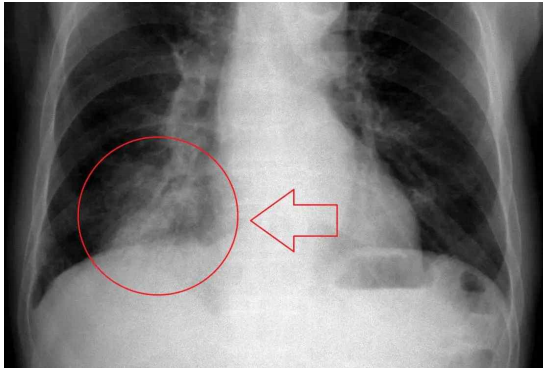

1) Chest X-ray

X-ray 검사를 통해 폐렴을 대엽성 폐렴, 기관지 폐렴, 소엽성 폐렴, 간질성 폐렴으로 분류할 수 있다.

세균성, 지역사회 획득 폐렴은 하나의 폐 분절엽(lung segmental lobe)의 페경화(lung consolidation)를 나타내지만, 결과는 다를 수 있으며 다른 유형의 폐렴에서는 다른 패턴이 일반적이다.

흡인성 폐렴 (Aspiration pneumonia) :

주로 폐의 기저부와 오른쪽에 혼탁함을 보인다.

바이러스성 폐렴 (Viral pneumonia) :

정상으로 보이거나, 과팽창되거나, 양측 반점 부위가 있거나, lobar consolidation(대엽 경화)을 동반한 세균성 폐렴과 유사하게 나타날 수 있다.

방사선학적 소견은 질병의 초기 단계, 특히 탈수가 있는 경우에는 나타나지 않을 수 있으며, 비만이나 폐 질환의 병력이 있는 사람들에서는 해석하기 어려울 수 있다.

흉막 삼출액(pleural effusion)과 같은 합병증은 흉부 방사선 사진에서도 발견될 수 있다. 측면 흉부 방사선 사진(*chest decubitus)은 폐 경화 및 흉막 삼출액의 진단 정확도를 높일 수 있다.